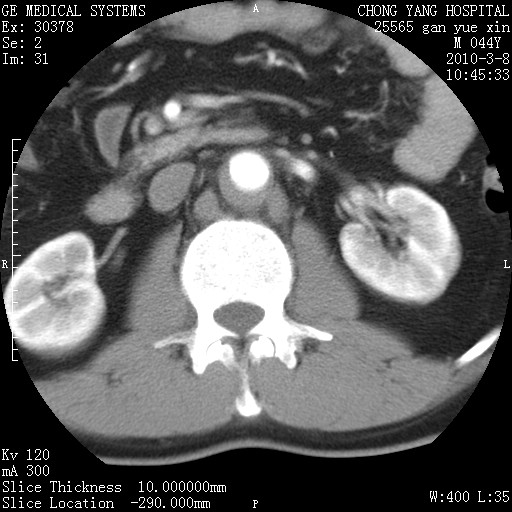

标题: CT24940:主动脉增强,典型病例。 [打印本页]

标题: CT24940:主动脉增强,典型病例。

夹层动脉瘤。

动脉夹层

夹层动脉瘤,典型

主动脉夹层。

动脉夹层的分型:

⒈debakey分型:根据主动脉夹层累及部位,分为三型:ⅰ型:原发破口位于升主动脉或主动脉弓部,夹层累及升主动脉、主动脉弓部、胸主动脉、腹主动脉大部或全部,少数可累及髂动脉。ⅱ型:原发破口位于升主动脉,夹层累及升主动脉,少数可累及部分主动脉弓。ⅲ型:原发破口位于左锁骨下动脉开口远端,根据夹层累及范围又分为ⅲa,ⅲb。ⅲa型:夹层累及胸主动脉。ⅲb型:夹层累及升主动脉、腹主动脉大部或全部。少数可累及髂动脉。

⒉stanford分型:a型:夹层累及升主动脉,无论远端范围如何。b型:夹层累及左锁骨下动脉开口以远的降主动脉。

夹层动脉瘤,少量胸水

夹层动脉瘤;左侧少量胸腔积液。

典型主动脉夹层。